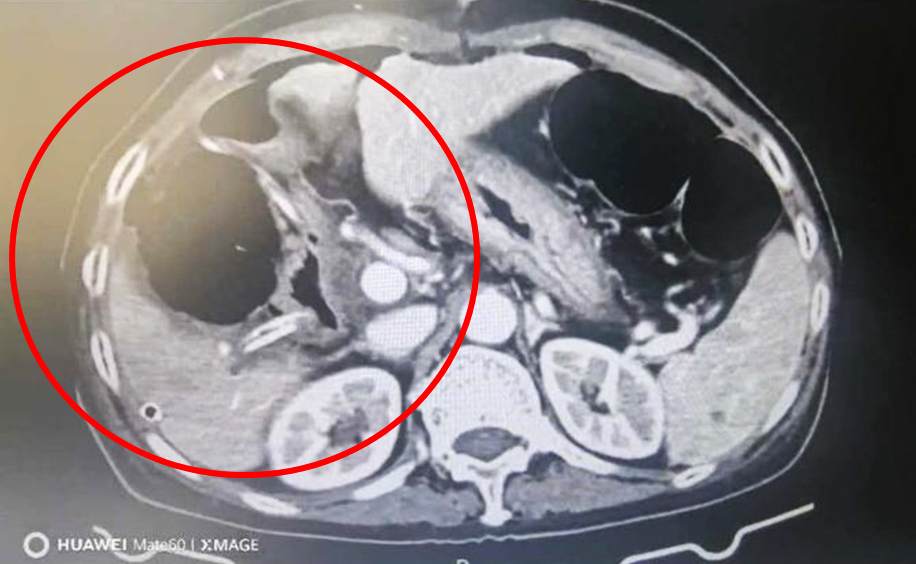

术后CT

术后,肝胆外科医护团队落实快速康复个体化方案,严密监测肝功能、凝血功能、生命体征及腹腔引流情况,精细化做好管路护理、疼痛管理、营养支持和感染防控。患者术后未出现大出血、肝功能衰竭、胆瘘、腹腔感染等并发症。第二天即下床活动,饮食逐步恢复正常。在医护团队的精心治疗和护理下,患者各项指标持续好转,最终顺利康复出院。